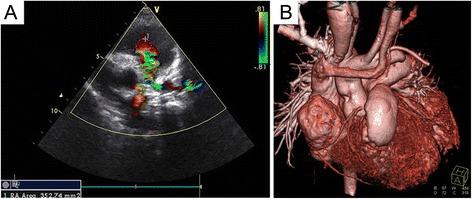

The pulmonary artery was reconstructed using autogenous tissue that had been preserved in situ and a bovine jugular venous patch in 24 patients who were diagnosed with PA-VSD (the observation group). The traditional operation using a bovine jugular venous conduit was performed in 40 other cases of PA-VSD (the control group).

In the observation group, all patients survived and recovered successfully without complications. Follow-up echocardiography 2-10 years after the procedure showed that the reconstructed right ventricular outflow tract (RVOT) and pulmonary artery were patent, showing no evidence of flow obstruction. Only mild regurgitation of the bovine jugular vein valve was observed. In the control group, early postoperative death occurred in two cases. Another two patients had obstruction of the anastomotic stoma and underwent conduit replacement surgery within 2 weeks of the initial procedure. During the 2-10 years of follow-up care, six patients presented with valvular stenosis of the BJVC, with a pressure gradient of more than 50 mmHg.